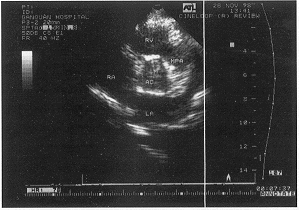

左室流出道粘液瘤致主动脉阻塞1例

李元玲 张启萍(200065 上海铁道大学附属甘泉医院心超室);王永武 曹克坚(胸外科)

患者男性 ......